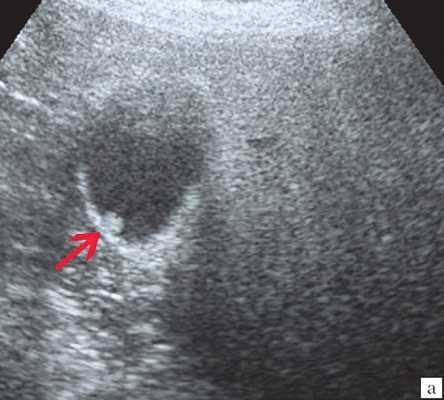

- УЗИ желчного пузыря. Эхогенная картина не слишком специфична и достаточно изменчива. На мониторе можно увидеть изменение структуры, толщины стенок, значительное увеличение объема пузыря. Внутри органа визуализируется скопление желчи, возможно с газовыми пузырьками, неоднородным осадком, хлопьями. В перипузырном пространстве обнаруживается выпот и скопление жидкости.